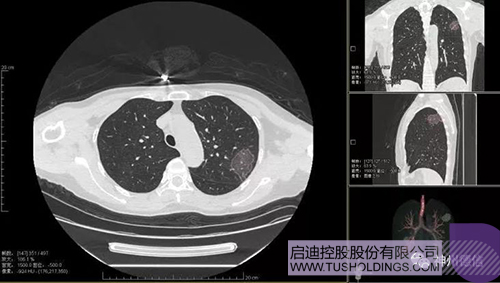

神州德信新冠肺炎检测及智能量化分析系统

乐动在线战略投资企业神州德信作为国内领先的肺部影像人工智能企业,针对新型冠状病毒肺炎开发了智能检测及量化分析系统,并在陕西、重庆等地定点医院投入使用。该系统在疑似病例大规模快速筛查及精准诊断方面发挥了重要作用,特别是其具有的肺炎患者临床影像跟踪量化随访功能,为快速有效阻断疫情扩散提供了有力武器。